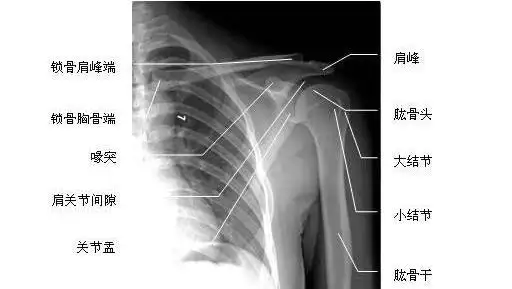

不同肩关节x线投照位

肩关节x线检查特殊体位